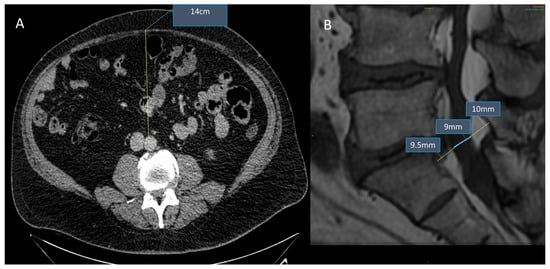

- Spinnato, P.; Barakat, M.; Lotrecchiano, L.; Giusti, D.; Filonzi, G.; Spinelli, D.; Pipola, V.; Moio, A.; Tetta, C.; Ponti, F. MRI Features and Clinical Significance of Spinal Epidural Lipomatosis: All You Should Know. Curr. Med. Imaging 2022, 18, 208–215. [Google Scholar] [CrossRef] [PubMed]

- Spinnato, P.; Lotrecchiano, L.; Ponti, F. “Y” sign in spinal epidural lipomatosis. Jt. Bone Spine 2020, 88, 105056. [Google Scholar] [CrossRef]

- Kuhn, M.J.; Youssef, H.T.; Swan, T.L.; Swenson, L.C. Lumbar epidural lipomatosis: The “Y” sign of thecal sac compression. Comput. Med. Imaging Graph. 1994, 18, 367–372. [Google Scholar] [CrossRef]